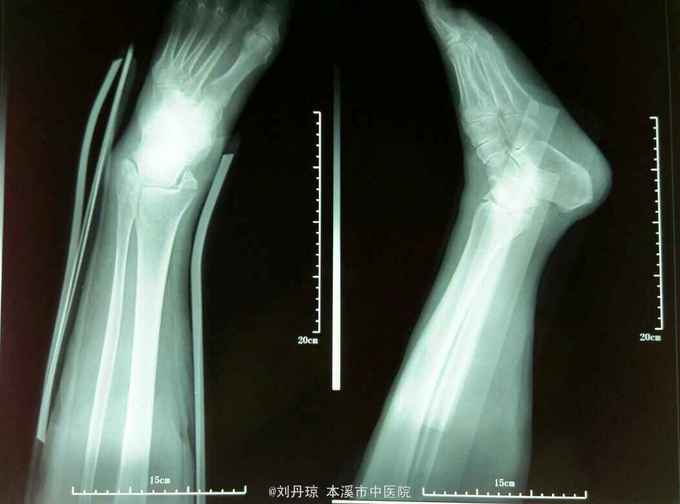

左踝关节畸形,肿胀明显,压痛阳性,左踝关节功能障碍。足背动脉搏动清,足趾活动良好。辅查:DR:左踝关节骨折,三踝骨折移位明显。

诊断:左踝关节骨折 旋后外旋型IV度 治疗:手法整复,活血膏外用,夹板固定。接骨丹口服。

随访1年。讨论:对于踝关节骨折脱位,治疗的目标,是将关节脱位解剖复位。并为此自骨折愈合,最终使踝关节恢复良好的功能。结果与踝关节解剖重建的好坏直接相关。治疗的手段,不外乎,包括保守治疗和手术治疗两种,近三十年来,由于人们对生活质量和功能结果的要求的提高。结果评价的标准,发生了变化,保守治疗,和手术治疗的适应症,有了明显的变化。闭合复位,对于某些,类型的环关节骨折脱位很难,达到和保持器解剖复位,为了丢失和反复长福,将影响治疗效果。另外长时间的制动,也可导致失用性骨质疏松,和踝关节僵硬。但这些通过适当的方法都是可以避免的。本例患者,经一次复位达到,维持解剖复位。本例患者由于全身条件的影响,患者不愿接受手术。故采用保守治疗。